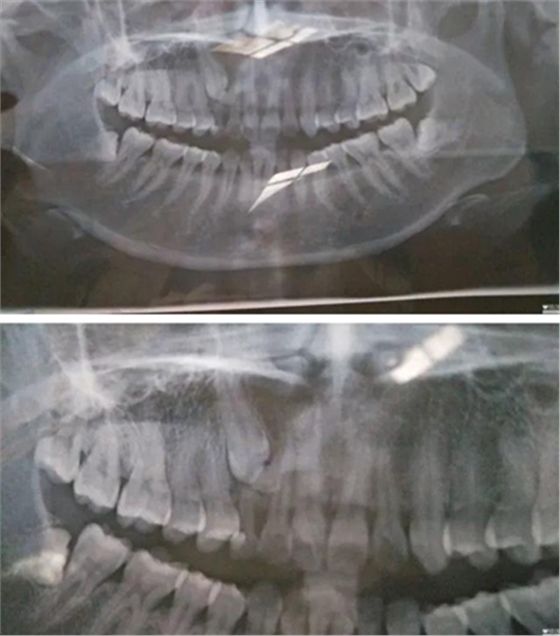

2017年6月18日,牙疼…之前補(bǔ)過一次,這次估計(jì)是發(fā)炎了,然后被伊森告知乳牙滯留,恒牙阻生,要拍片確認(rèn)恒牙是否完好,才能進(jìn)行下一步…鎮(zhèn)醫(yī)院,設(shè)備不齊全,伊森建議去大醫(yī)院拍片…

心里著急,第二天就跑到廣東省口腔醫(yī)院花了一天的時(shí)間排隊(duì)拍片,然后被伊森建議去矯正科詳細(xì)咨詢…然后矯正伊森就跟我說了大概治療方案,時(shí)間和費(fèi)用,先拔掉四顆智慧牙,然后帶牙套矯正牙齒,期間會(huì)拔掉小虎牙給埋伏牙做牽引(我情況比較復(fù)雜,下面有兩顆埋伏牙,還得拔掉其中一顆)╭(°A°`)╮而且還不一定牽引成功,如果不成功,最后矯正后期還要種植牙齒(?_?)…要花3-4W,長達(dá)2年時(shí)間…當(dāng)時(shí)就震驚了,從沒想過自己這口牙辣么貴,辣么麻煩…

跟LG一起確定了矯正之后,立馬打電話給伊森預(yù)約了7.3號(hào),然后LG陪我一起去了醫(yī)院,伊森詳細(xì)了解了婚姻狀況,生娃狀況(對(duì)于我已經(jīng)有兩個(gè)娃的事實(shí)表示了各種驚訝),然后拍片,倒模具,定制方案,約定下次就診時(shí)間…

然后被伊森告知了一個(gè)不好的消息,(?_?)我乳牙下面的牙經(jīng)集體開會(huì)討論一直認(rèn)為牽引不上來,需要矯正完成后去種植,費(fèi)用要1-1.5W,瞬間心都涼了T^T,期間繼續(xù)不死心的重復(fù)問可不可以牽引,估計(jì)所有人都會(huì)覺得牙齒還是原配的好…結(jié)果還是令我失望〒_〒